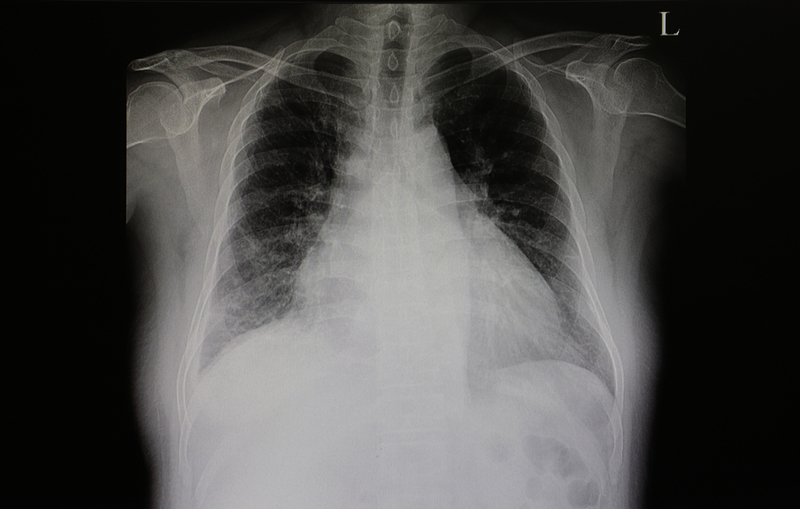

Classifying patients with acute heart failure according to congestion/ hypoperfusion provides clinically relevant information both at hospital admission and at discharge.

In a Cox-proportional hazard model with multivariable adjustment, based on classification at admission, ‘wet-warm’ was not worse than ‘dry-warm’ for in-hospital mortality, suggesting that congestion can be addressed in hospital. However, hypoperfusion on admission was associated with in-hospital mortality. Using classification at discharge, both hypoperfusion and congestion were associated with one-year mortality. Nearly one-third (30.9%) of patients with acute heart failure discharged from hospital had residual congestion.

One-year mortality was higher in patients with vs without congestion at discharge (28.0% vs 18.5%).

The finding regarding congestion is particularly important, according to Dr. Chioncel. “Congestion on discharge, even to a minor degree, is associated with poor prognosis and treatment of residual congestion should be addressed as a matter of priority. The classification system may help to ensure that congestion, which may otherwise be overlooked, is identified and can be managed appropriately.” He recognises that while the congestion/hypoperfusion system is a big step forward in standardising classification, it cannot be used in isolation. Instead, it should be supported by information from biological variables, such as natriuretic peptic levels, particularly in patients without evident clinical signs of congestion. He also acknowledges that clinical signs of hypoperfusion are not well understood and that doctors may only be aware of it following cardiogenic shock. “There needs to be greater understanding of hypoperfusion so that it is possible to anticipate and prevent a potential cardiogenic shock,” he says.